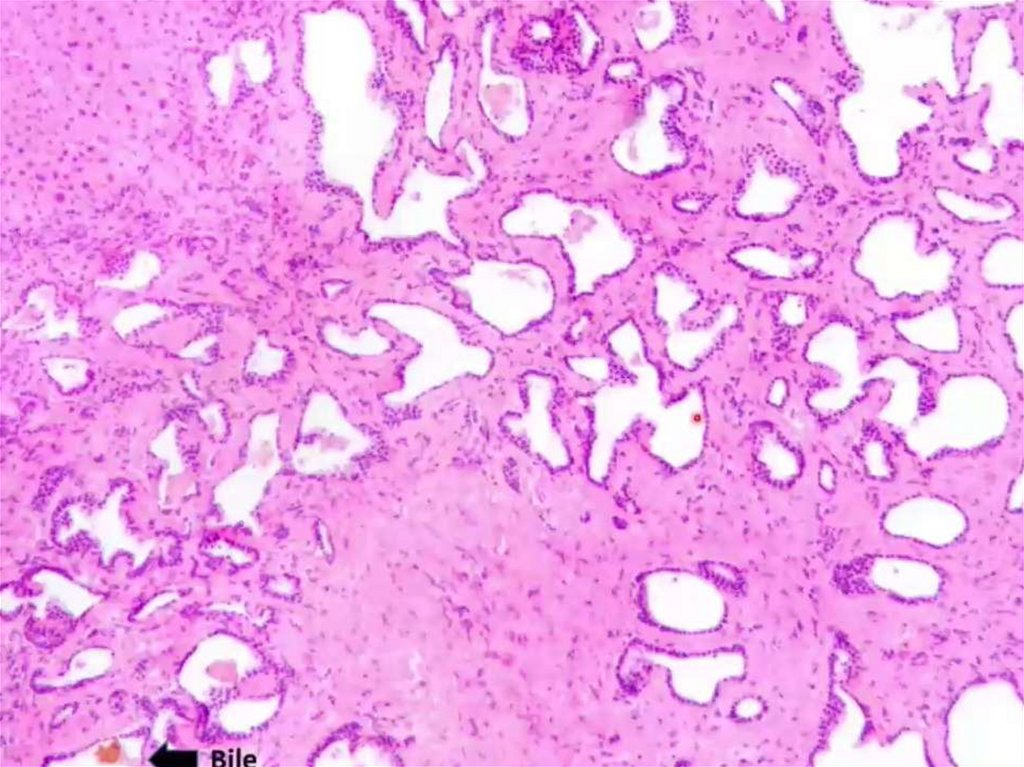

Cholangicarcinoma